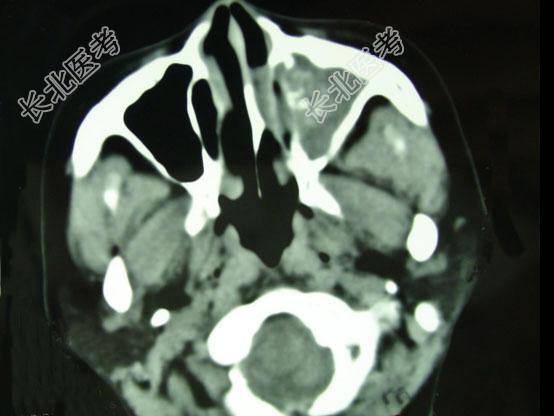

- 单项选择题男,41岁, 左侧鼻腔胀痛半年余,CT检查如图, 最可能的诊断是 ( )

A、出血坏死性息肉

B、化脓性鼻窦炎

C、过敏性鼻窦炎

D、真菌性鼻窦炎

E、上颌窦癌